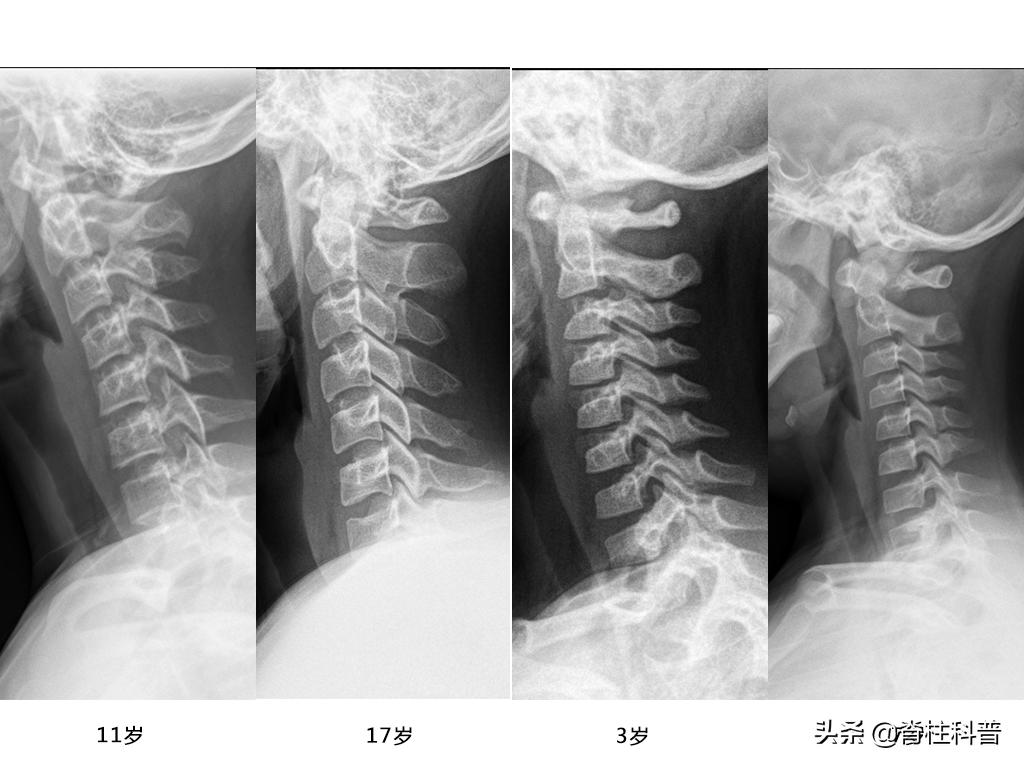

同理,在现在的中小学生的学习生活中,电子产品(如ipad、学习机等)的应用,使得学生不得不长期处于低头状态。从小开始养成的低头习惯,使得越来越多的中小学生因为颈痛、头痛等原因前来就诊。通过拍X光发现,他们的颈椎生理曲度已开始改变。令人十分可惜!